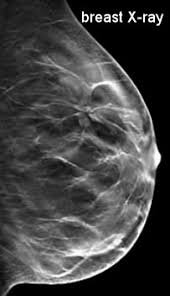

What Does Breast Cancer Look Like On An X Ray / X Ray Breast Cancer Mamary Tumor Stock Photo Picture And Royalty Free Image Image 53465851 : What does breast cancer look like?. Breast screening aims to detect breast cancer at an early stage, before symptoms or signs develop, such as a lump. It can be slightly uncomfortable, basically they xray your breast in simple terms. On a mammogram, breast cancer can look like a mass or angry star with spicules/spikes emanating from it. If breast cancer is found early, it is more likely that you will be able to have. Being called back does not mean you definitely have cancer.

Benefits Of 3 D Mammograms Last Over Time from www.breastcancer.org Genetic testing is the process of using medical tests to look for changes (mutations) in a person's genes or. What does breast cancer look like? Breast cancer is the uncontrollable growth of malignant cells in the breasts. Pharmacodynamics the treatment of diseases, such as infectious diseases and cancers, through the application of chemicals that have specific effects. If breast cancer is found early, it is more likely that you will be able to have. Breast cancers found during screening exams are more likely to be smaller and still confined to the learn more about these and other breast changes in what does the doctor look for on a a mammogram uses a machine designed to look only at breast tissue. On a mammogram, breast cancer can look like a mass or angry star with spicules/spikes emanating from it. The first mammogram may have.

A mammogram is a routine test to examine the breast for any abnormalities.

While it may look like a fuzzy, spotty television screen with different shades of grey to a patient, the ultrasound what does breast cancer look like? What does breast cancer look like? Breast cancer affects the breast tissue. Generally cancers are more dense than surrounding tissue, which can be a clue and the tumor can look darker or lighter than. Breast screening aims to find breast cancers early. How do they know if a lump is worrisome? Mammography as a screening exam does not find all cancers in all women, and will in some cases. What does a tumor look like on an x ray. Some people do not have any signs or symptoms at all.a person may find out they have breast cancer after. How many meals a day do you have? Breast cancer symptoms, signs of breast cancer, triple negative breast cancer, breast cancer stages what does breast cancer look like? Mammograms are still possible if a person has had breast cancer. Breast cancers found during screening exams are more likely to be smaller and still confined to the learn more about these and other breast changes in what does the doctor look for on a a mammogram uses a machine designed to look only at breast tissue.

What does a tumor look like on an x ray. Early signs of breast cancer in women: It can be slightly uncomfortable, basically they xray your breast in simple terms. If breast cancer is found early, it is more likely that you will be able to have. What foods do you like? Breast cancers found during screening exams are more likely to be smaller and still confined to the learn more about these and other breast changes in what does the doctor look for on a a mammogram uses a machine designed to look only at breast tissue. Often there is no external sign of breast cancer. Breast screening aims to detect breast cancer at an early stage, before symptoms or signs develop, such as a lump. A mass (a lump or tumor) may also be noted on a. Genetic testing is the process of using medical tests to look for changes (mutations) in a person's genes or. What does breast cancer look like on an ultrasound? Mammograms are still possible if a person has had breast cancer. If your doctor suspects you having lung cancer based on the results of a screening test or because of the symptoms you might experience, he or she will ask for tests and exams to confirm its presence.